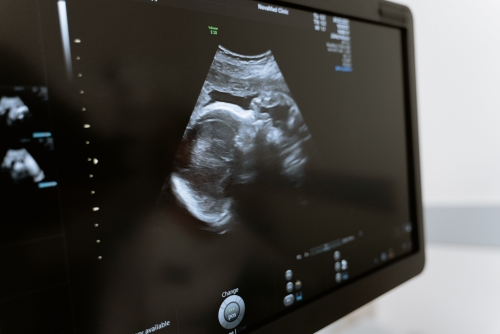

懷孕做超聲檢查得多久才能完成—平創醫療

懷孕做超聲檢查通常需要10-20分鐘,根據檢查的不同,檢查時間可能會有所差異。進行超聲檢查時,通常需要暴露腹部,穿過腹部脂肪,將探頭放于腹部不同層次,從不同的方位進行超聲診斷。

1、胎兒檢查:對于懷孕早期的胎兒檢查,通常需要5-10分鐘,因為此時胎兒較小,而且羊水適量,胎兒在子宮內活動度較大,可以觀察得比較清楚。如果是中晚期,則胎兒較大,可能會遮擋一些部位,超聲檢查時間會相應延長;

2、多普勒超聲檢查:通常需要10-20分鐘,一般用于頸部血管、心臟等檢查,可以觀察到血流情況。如果胎兒發育存在畸形或者是心臟等問題,通過多普勒超聲檢查,可以觀察到血流動力學改變,從而評估胎兒的安危情況;

超聲檢測2

3、臍帶檢查:通常需要5-10分鐘,可觀察臍帶的搏動情況以及有無臍帶繞頸等情況。若出現臍帶繞頸等情況時,需根據臍帶繞頸的周數、臍帶的松緊程度,以及臍帶血管的直徑等,評估臍帶的血流情況,從而決定是否需要進行后續的產檢;

4、胎心監護:一般需要10-20分鐘,可觀察胎心率有無異常,還可以觀察胎心波動情況。正常胎心率為120-160次/分,如果胎心率小于120次/分或大于180次/分,可能提示胎兒在宮內存在異常情況,需要及時進行相應處理。

產檢過程中超聲檢查較為重要,建議孕婦定期進行超聲檢查,以了解胎兒在宮內的發育情況。